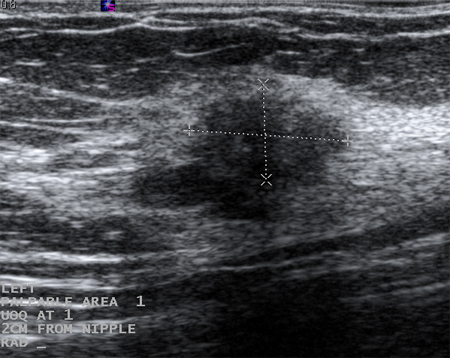

Ultrasonographic image of a fibroadenoma

Courtesy of Dr Lane Roland, University of Louisville; used with permission